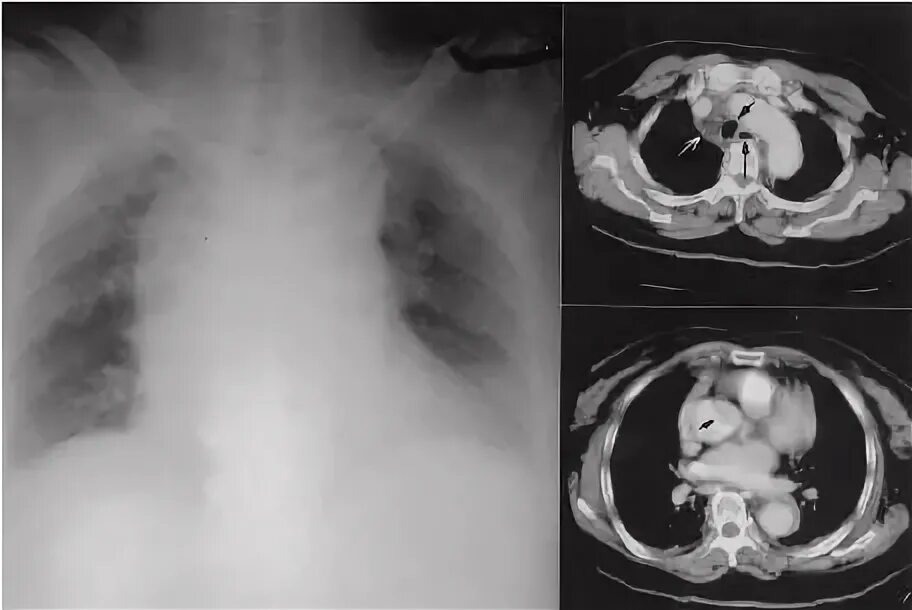

Медиастинит причины